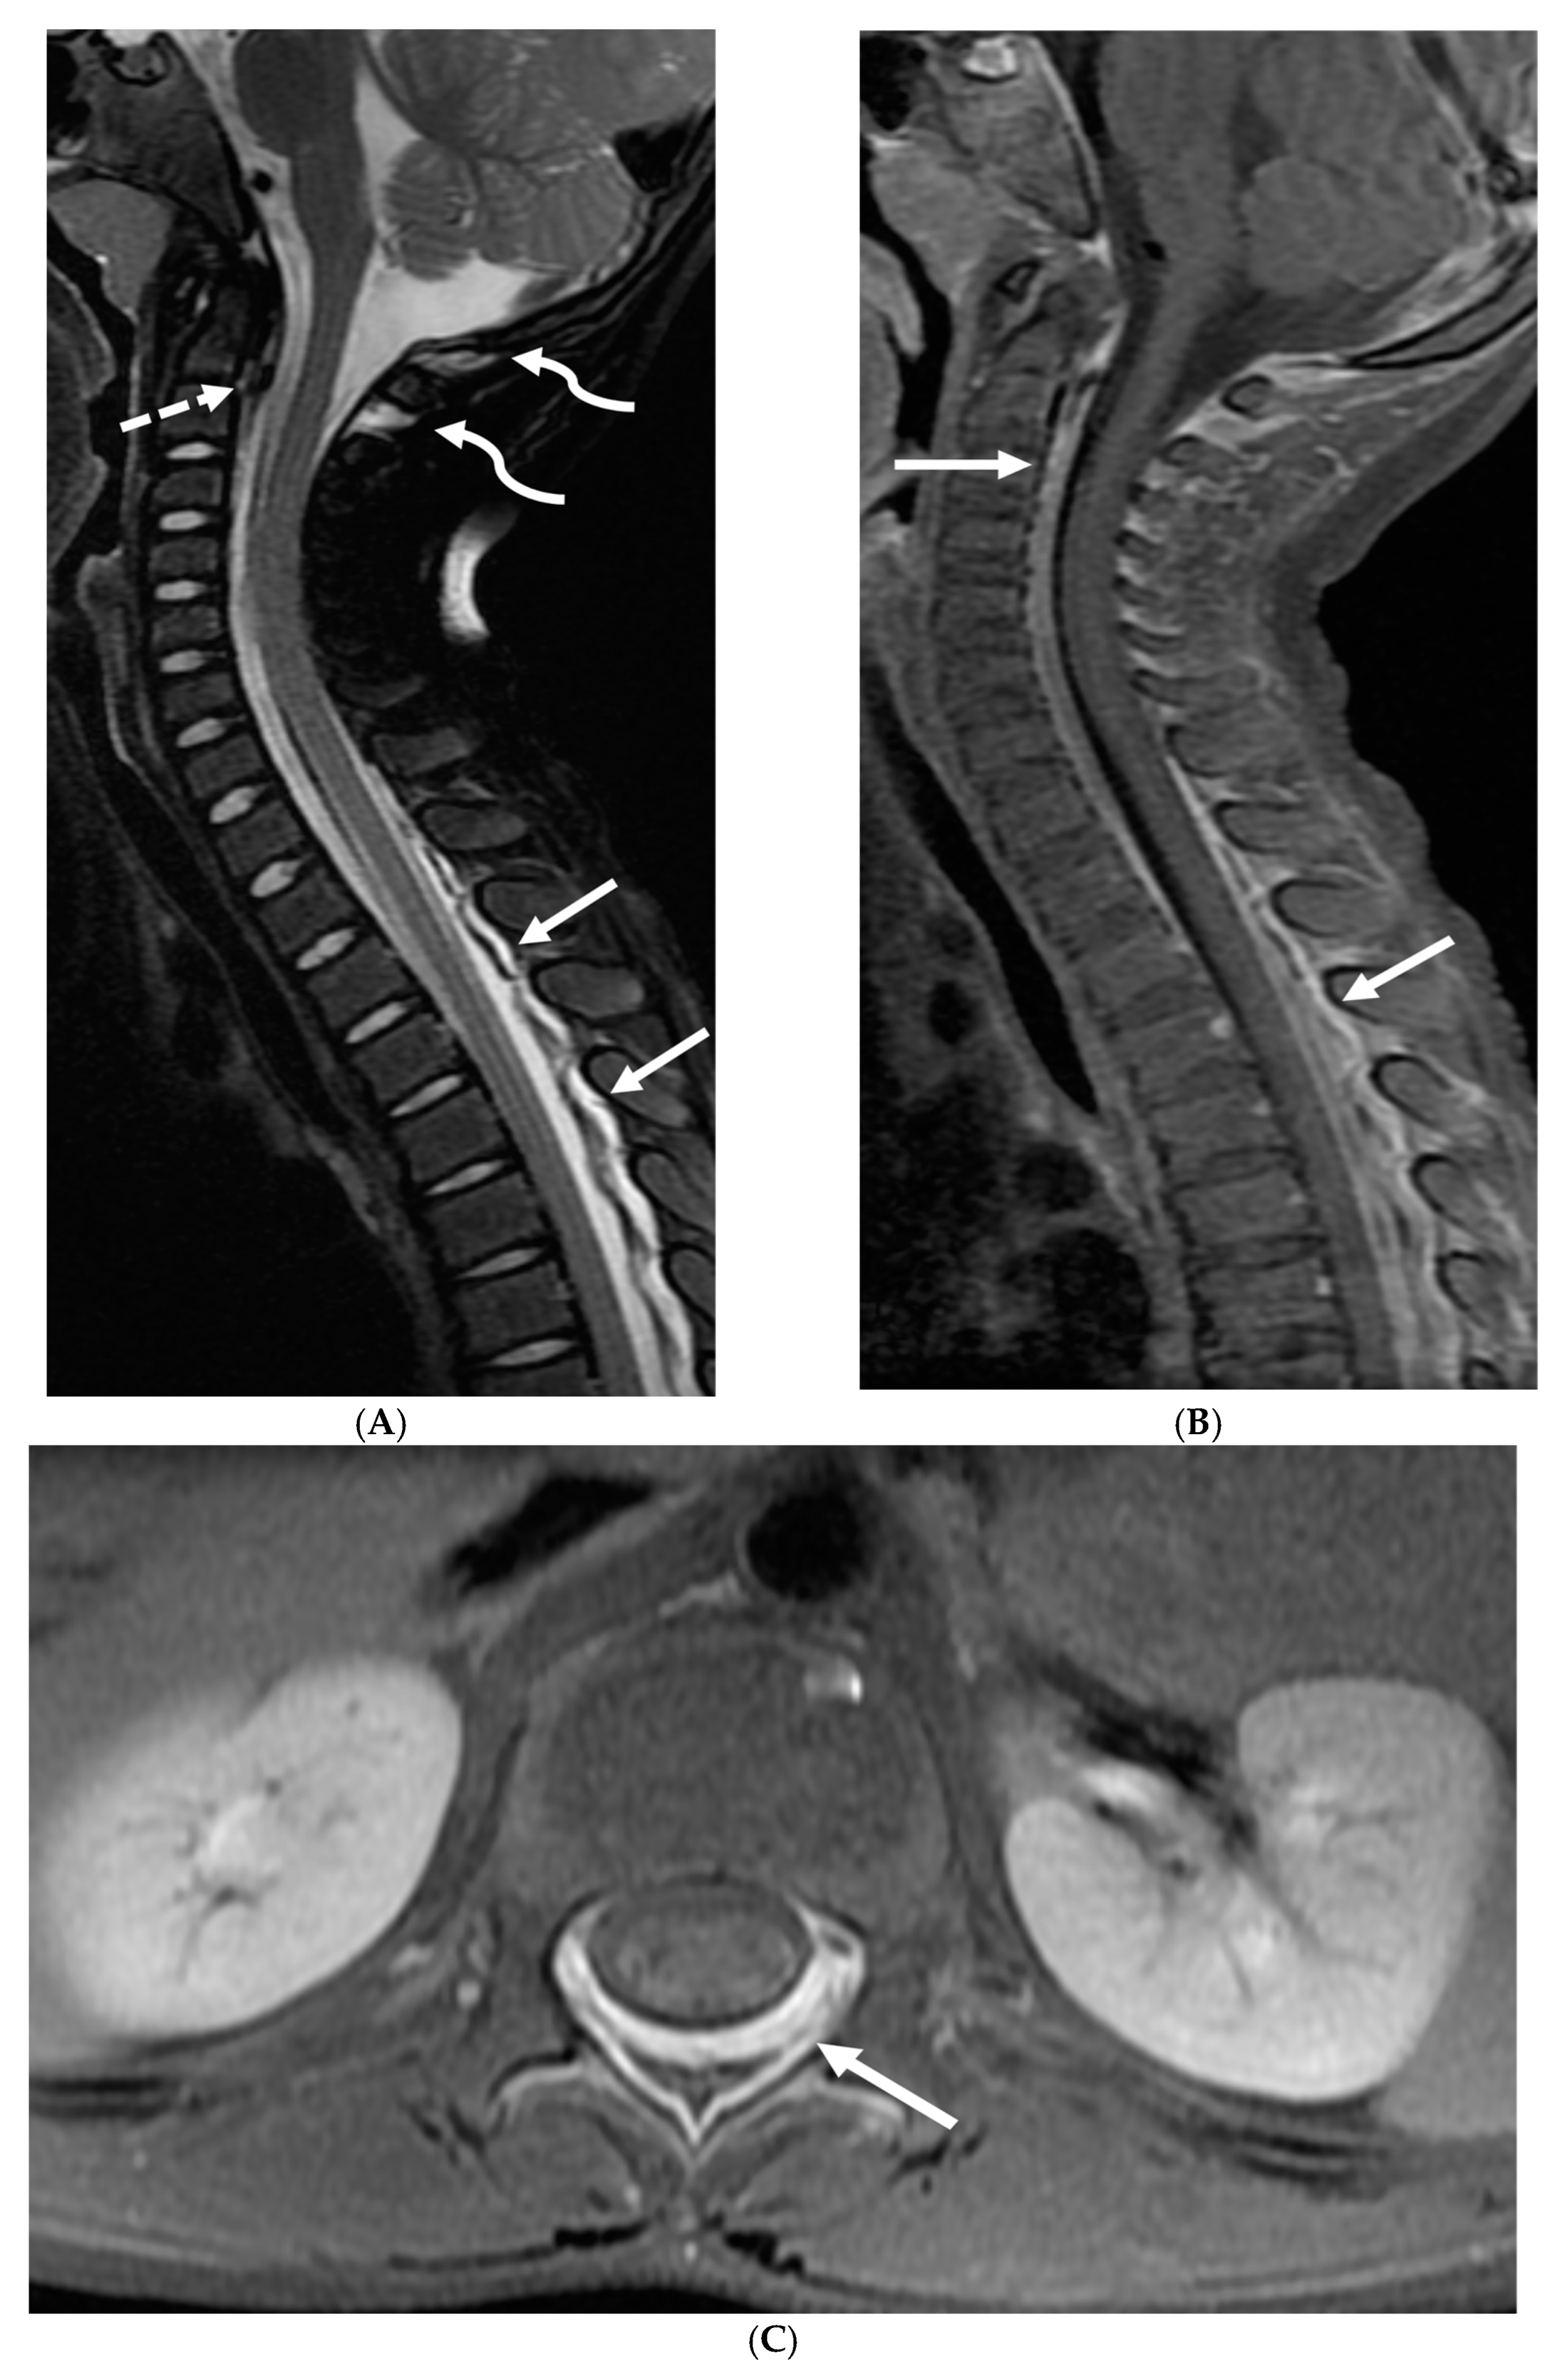

Marked focal nodularity and mass effect causing a deformed contour on the spinal cord favor a neoplastic process (Figure 7) [62]. Accurate staging is crucial as the presence of leptomeningeal or multifocal disease have implications on radiotherapy fields and total dose. Additionally, PET-CT scan assists in evaluating for an extracranial primary site [63].

Figure 7.

3-year-old boy with 2 weeks history of headache and vomiting. Axial FLAIR (A), post contrast axial T1 FS (B) and sagittal 3D inversion recovery (C) images demonstrate FLAIR hyperintensity in the interpedencular cistern (curved arrow) and mild hydrocephalus. Extensive meningeal enhancement most prominent at the skull base, basal cisterns, and Sylvain fissures (arrows), but extending throughout the brain. There is meningeal enhancement, with coating of the brainstem extends inferiorly along the cervical spinal cord (dashed arrows). Sagittal T2 (D), sagittal T1 (E) and fat saturated T1 post (F) images show extensive leptomeningeal with predominantly solid and some cystic nodules (curved arrows) on T2 sequence and isointense on T1 (arrows). Lesions predominantly involve the posterior spinal canal, causing mass effect and anterior displacement of the spinal cord. The solid nodules show enhancement after contrast injection and extensive uniform diffuse LME around the cord (dashed arrows). Pathology: Primary Meningeal Rhabdomyosarcoma.